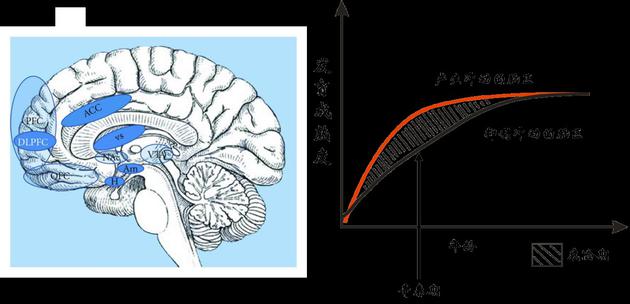

大脑中产生冲动和抑制冲动的脑区(左图)。青春期前后的一段时间内,产生冲动的脑区其发育成熟度要大于抑制冲动的脑区(右图)。处于这个年龄段的青少年往往难以控制冲动、冒险、反叛等行为,并忽视这些行为可能对自己带来的危险

大脑中产生冲动和抑制冲动的脑区(左图)。青春期前后的一段时间内,产生冲动的脑区其发育成熟度要大于抑制冲动的脑区(右图)。处于这个年龄段的青少年往往难以控制冲动、冒险、反叛等行为,并忽视这些行为可能对自己带来的危险青少年不是完全不能玩电子游戏,要警惕的是沉溺于游戏。千万不能因为玩游戏而影响到正常的学习和生活,对身体和大脑的发育带来负面影响。一项来自西班牙的研究发现:小学生一周玩一小时电子游戏不仅没有害处,反而有助于提高手眼反应能力和在学校的行为表现;但如果每周玩电子游戏超过5-6个小时,就会带来负面影响。除了控制玩游戏时间的长短、做到定时定量以外,家长们还能做的就是成为孩子们的玩伴,陪他们一起玩。陪孩子玩游戏可以增进跟他们之间的沟通与交流;也只有在成为他的玩伴或队友时,家长才有可能了解自己孩子玩网络游戏的动机、心理及感受,才有可能正确引导孩子分清楚虚拟世界和现实世界。此外,多带孩子参加一些课外活动,培养孩子除游戏以外的兴趣爱好,也很有帮助。 最后,还有一条我个人觉得非常重要,就是不能把“玩游戏”当做让孩子写作业、干家务的奖励和砝码。这样做往往会适得其反,让孩子为了获得玩游戏的机会而“被利诱”或“屈服”,增加他们对游戏的渴望。